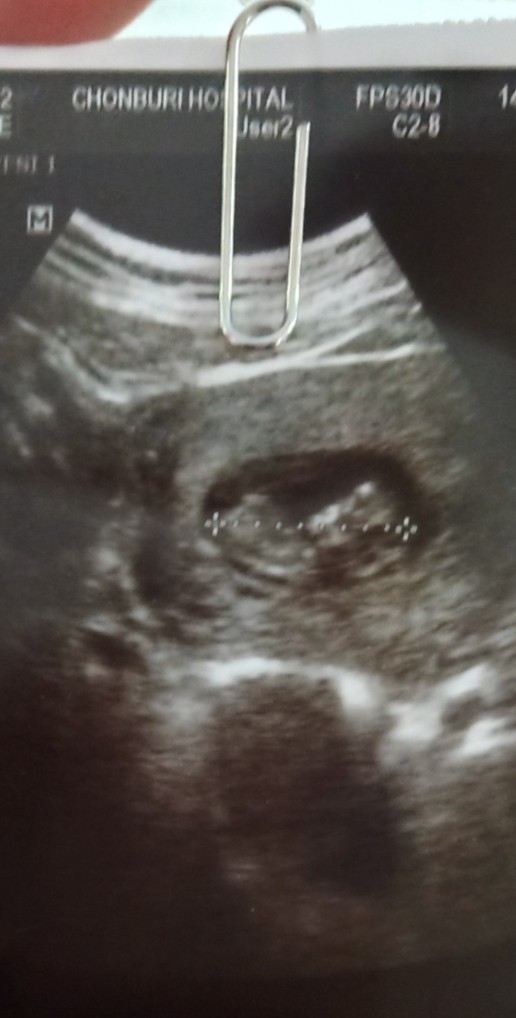

อ้าขาเลย ผู้หญิงค่ะ

มีกลีบเหมือนกันจ้า

บ้านนี้กลีบค่ะ